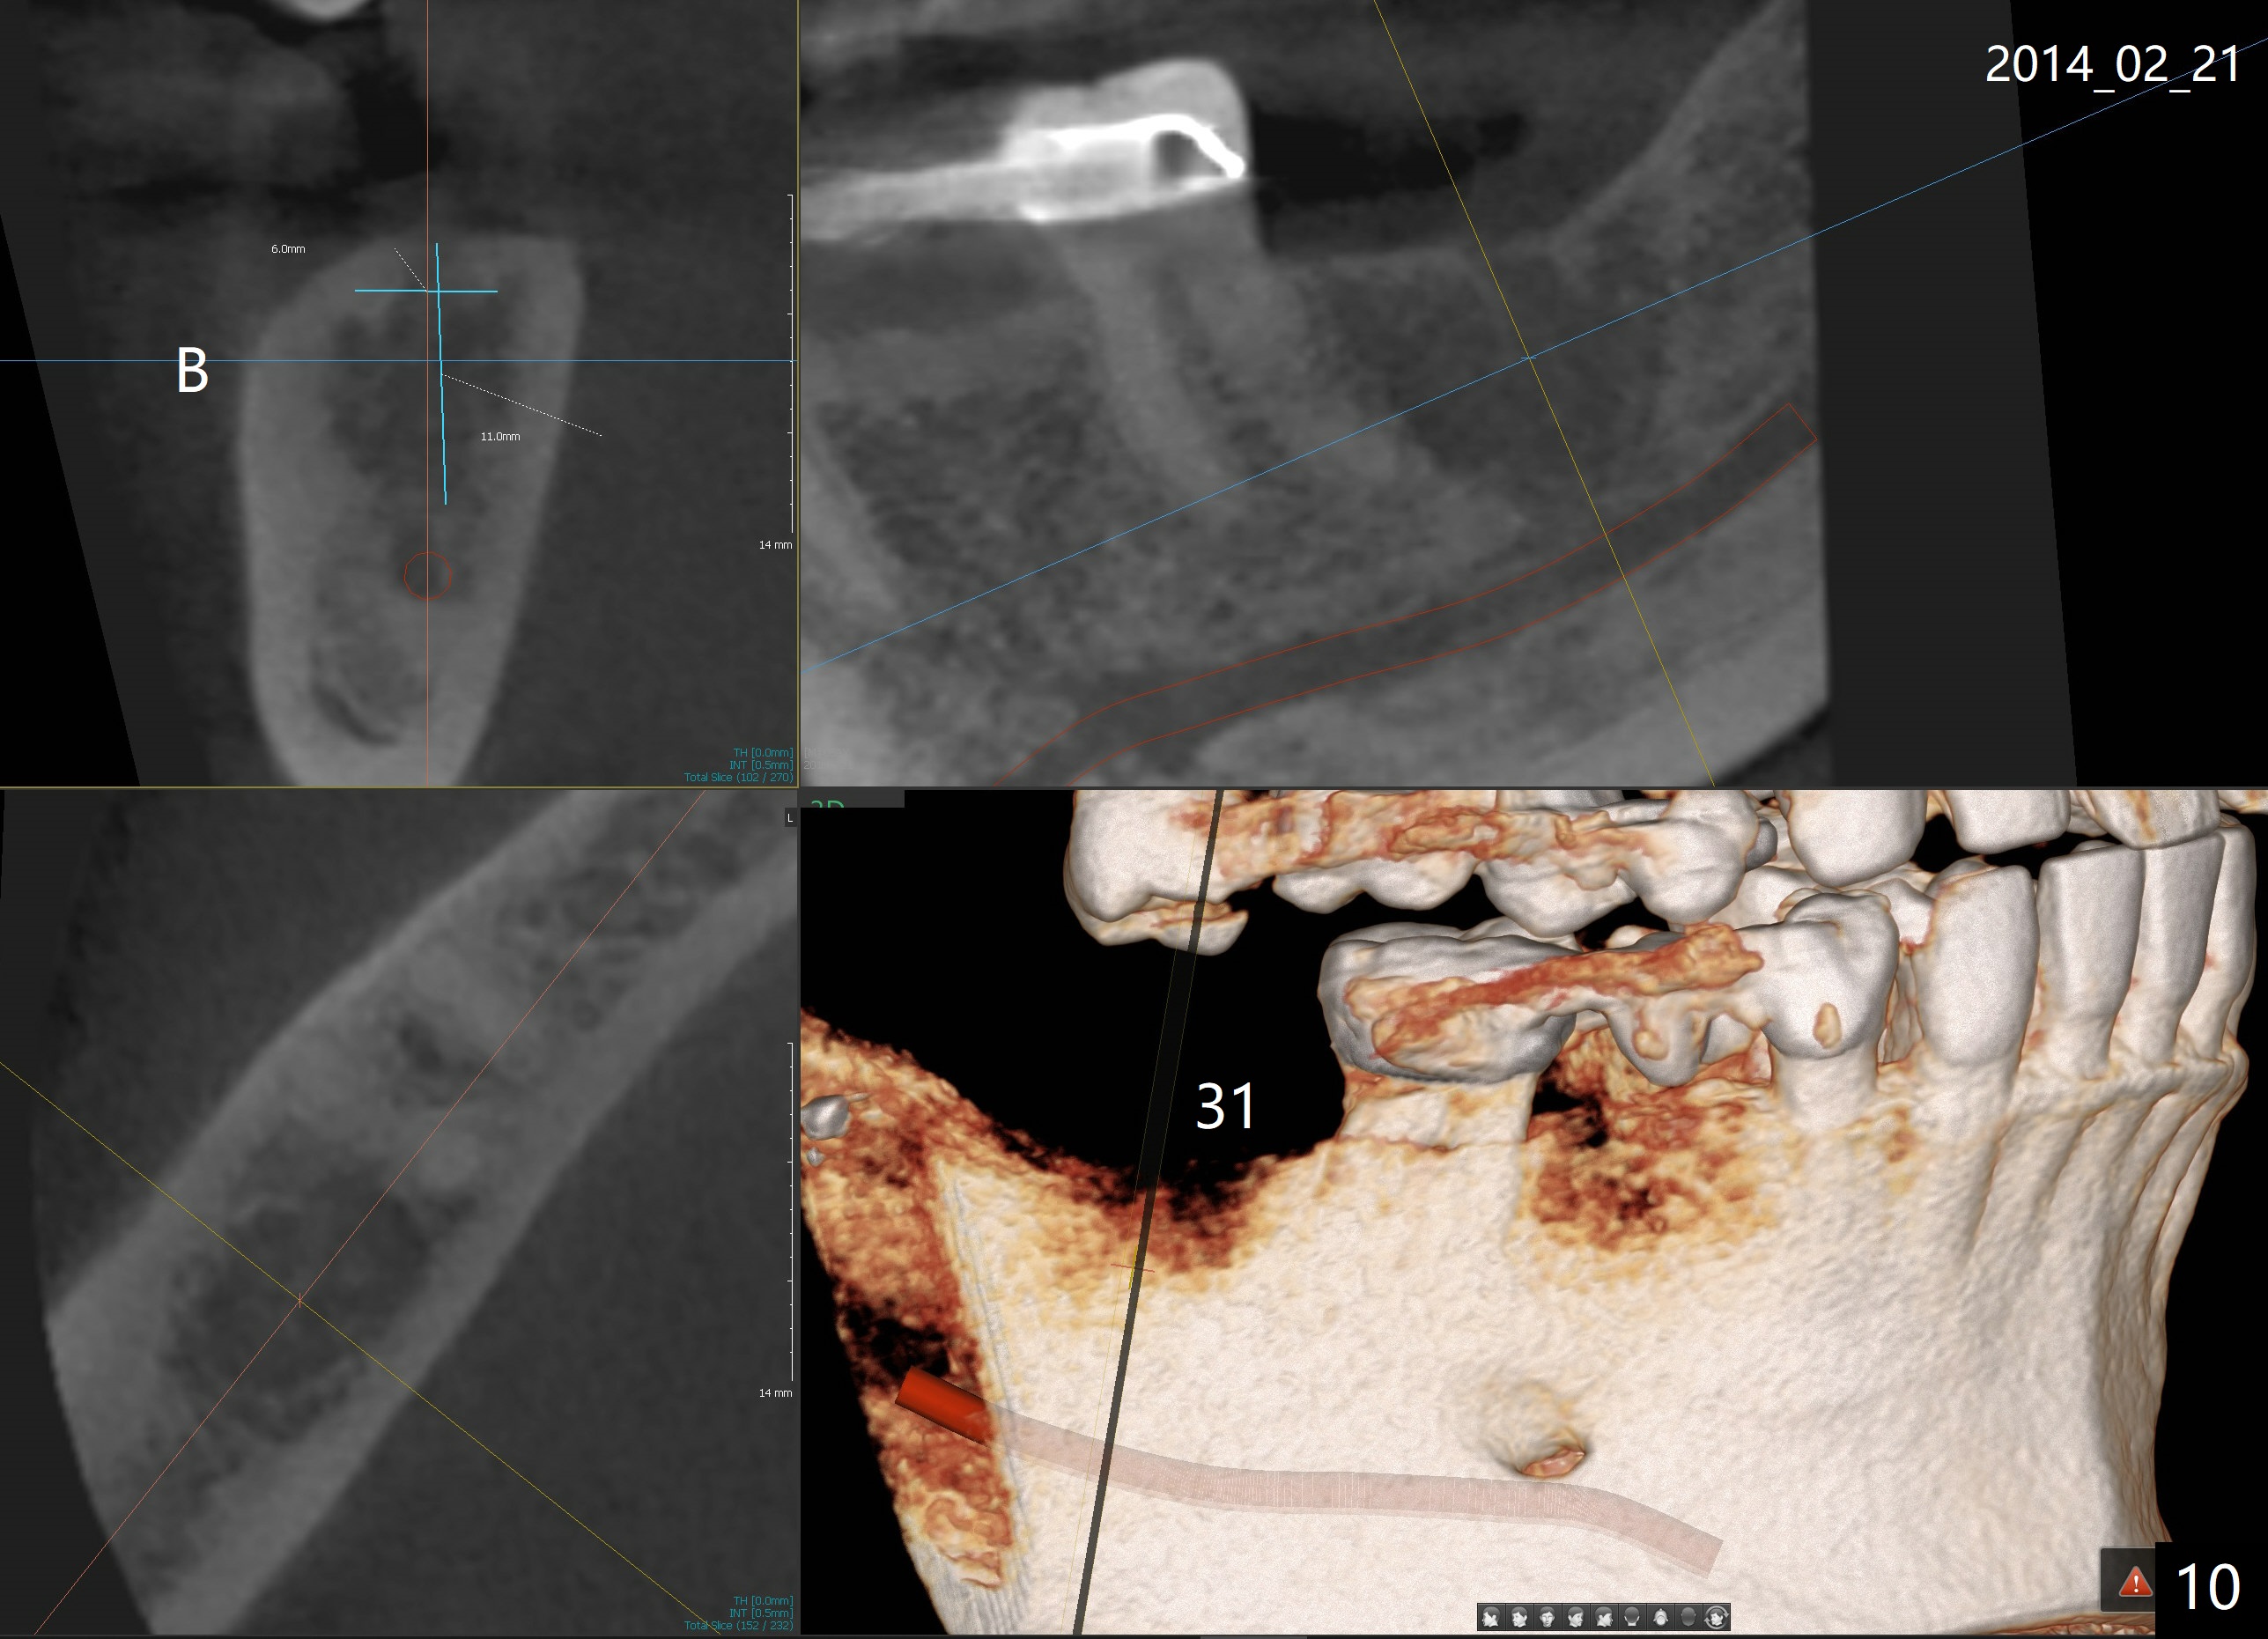

A 51-year-old man requests taking care of hemorrhage and odor associated with the tooth #3 (Fig.1). Due to religious and financial issues, the neighboring teeth will be treated later (supraeruption of #2 (arrow) and periapical radiolucency of #4 (*)). CBCT reveals that the septum of #3 is large enough to hold 4.5 mm implant (Fig.2). In fact osteotomy is created as planned in the septum using drills and taps (Fig.3 after removing 4.5x20 mm tap). Primary stability is obtained with a 4.5x20 mm implant (> 60 Ncm, Fig.4). The gap (*) is bone grafted; an abutment is placed (Fig.5 A); an immediate provisional is fabricated and cemented to cover the socket (Fig.6 P). When the socket heals in 3 weeks postop, the provisional and the abutment are removed for easy oral hygiene. Bone regenerates around the implant 3.5 months postop (Fig.7 *), but the 2nd molar has shifted mesially (arrow), presenting a restoration challenge.

It appears that the upper molar shifting is quite common (6 7), probably due to less dense bone in the maxilla. It is the best to fabricate and keep an immediate provisional to hold the mesiodistal dimension and ask the patient to improve local oral hygiene during osteointegration. The implant crown is functioning 4 years 2 months post cementation while there is severe bone loss at #2 (Fig.8). An immediate implant could be placed at #2 (Fig.9), while a wide delayed implant will be placed at #31 (Fig.10).